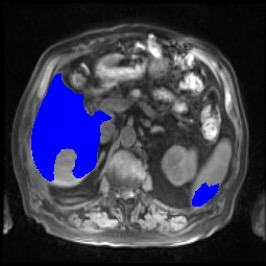

Integrating high-level semantically correlated contents and low-level anatomical features is of central importance in medical image segmentation. Towards this end, recent deep learning-based medical segmentation methods have shown great promise in better modeling such information. However, convolution operators for medical segmentation typically operate on regular grids, which inherently blur the high-frequency regions, i.e., boundary regions. In this work, we propose MORSE, a generic implicit neural rendering framework designed at an anatomical level to assist learning in medical image segmentation. Our method is motivated by the fact that implicit neural representation has been shown to be more effective in fitting complex signals and solving computer graphics problems than discrete grid-based representation. The core of our approach is to formulate medical image segmentation as a rendering problem in an end-to-end manner. Specifically, we continuously align the coarse segmentation prediction with the ambiguous coordinate-based point representations and aggregate these features to adaptively refine the boundary region. To parallelly optimize multi-scale pixel-level features, we leverage the idea from Mixture-of-Expert (MoE) to design and train our MORSE with a stochastic gating mechanism. Our experiments demonstrate that MORSE can work well with different medical segmentation backbones, consistently achieving competitive performance improvements in both 2D and 3D supervised medical segmentation methods. We also theoretically analyze the superiority of MORSE.